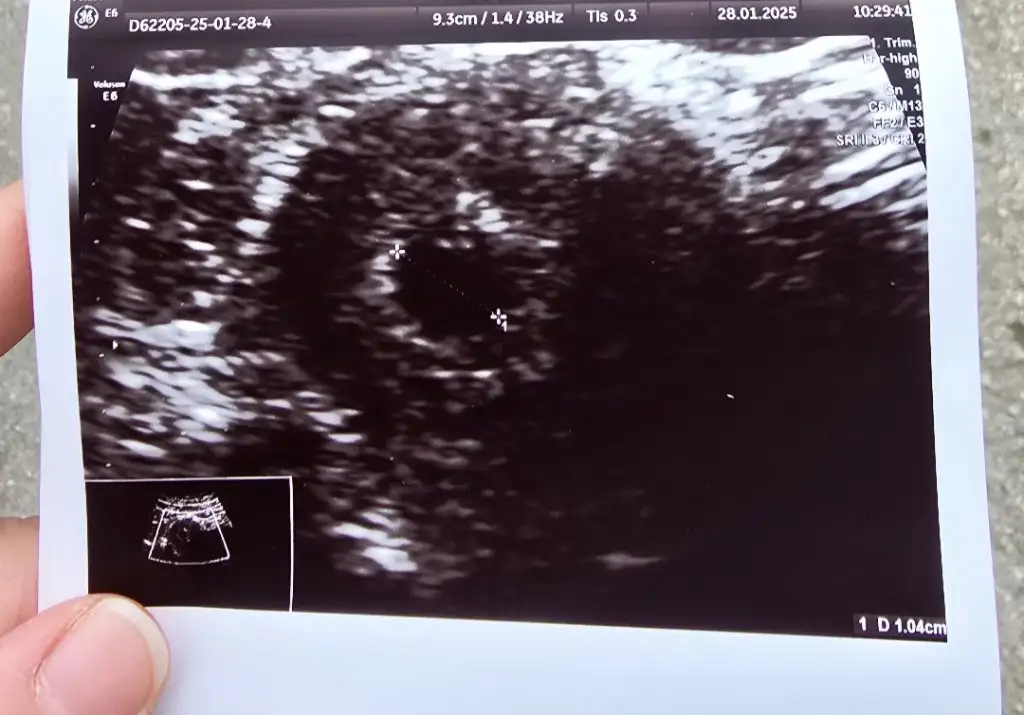

Bugün kese 5.5 mm göründü bebek görünmedi normal mi ? Vajinal bakıldı

28 ocakta tam 5 haftalık dedi kese göründü 10 mm